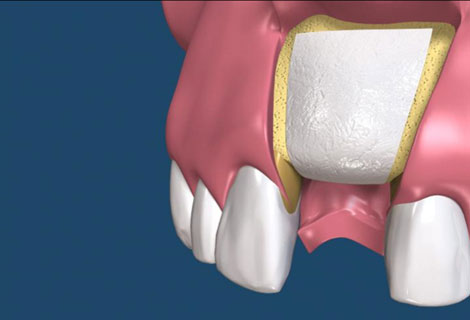

• 假牙製作階段

植體接出後,給予臨時假牙試戴,進行調整咬合與美觀部位的修飾,待病人適應一段時間後,依據調整好的咬合狀態進行印模製作永久假牙。(圖01-03)